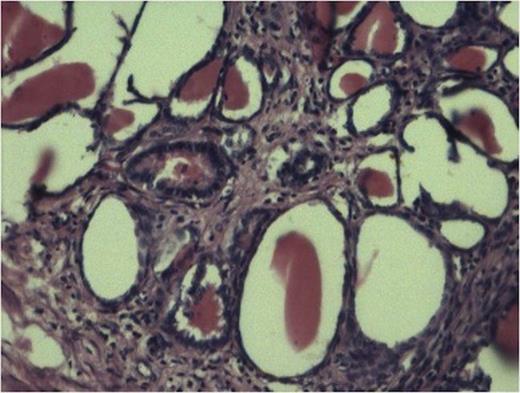

Tubules showing thyroidisation favouring chronic pylonephritis. (100x H and E stain).

The sections from various representative areas revealed dilated pelvicalyceal system lined by metaplastic squamous epithelium and shows changes of chronic pyelonephritis (Fig 2).